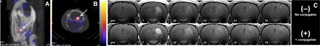

A) sagittal and B) axial SPECT images showing accumulation of radionuclide- labeled antibody conjugates in EGF receptor-expressing tumors. Arrows indicate position of the tumor. C) sequential MRI brain images of EGF receptor-expressing tumors after the injection of a peroxidase specific imaging probe in vivo; (–) temporal washout of imaging probe with no pre-injection of targeted peroxidase enzyme- anti-EGF receptor antibody conjugates; (+) washout of the same probe following the injection with anti-EGF receptor conjugates in the same MRI matched slices. © ISMRM